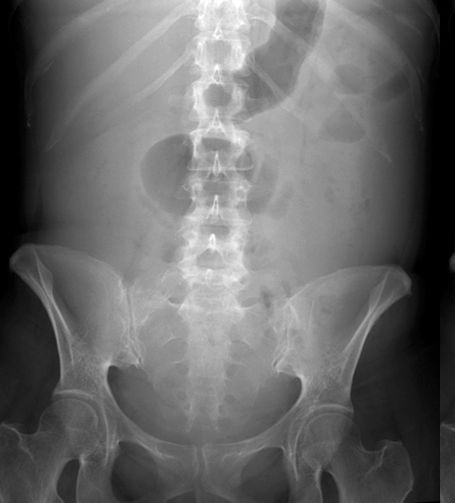

pt w/ ascites

what is this an image of?

ascites

accumulation of fluid in the peritoneal cavity

idiopathic

complication of trauma

perforate ulcer

appendicitis/inlfammation fo colon

what causes ascites?

additive → may have to increase technique

what is teh technique factors of a patient w/ ascites?